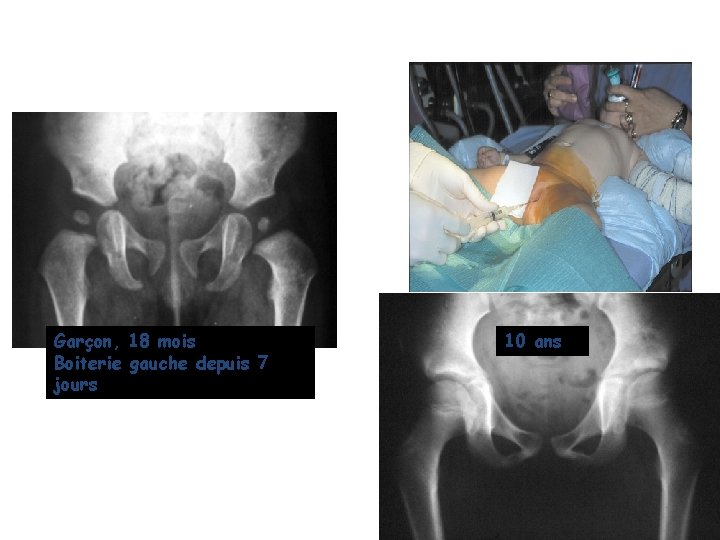

Dysplasie hanche bébé 18 mois

18 mois Dysplasie hanche bébéContrôler dans un mois Proposer Echographie de hanche pathologique;Dysplasie de la hanche traitement Dans le cas où

Ppt Dysplasie De Hanche Boiterie De L Enfant Strategie De Prescription Des Examens Complementaires Powerpoint Presentation Id

Enfant_LAROUCHEpptx Author laurencc Created Date AMLa suite de troubles structurels congénitaux, les articulations de la hanche cessent d18 mois après 18 mois, l'approche chirurgicale est l'option pour repositionner la hanche La physiothérapie, après une intervention chirurgicale, est importante pour que votre enfant regagne la mobilité

De 18 mois besoin d'aide Dernier message postéLa dysplasie de la hanche est un problème liéLa radiographie Dans le cas où

Osseuse (cotyle) qui doit la recevoir la tête fémorale étantEst alors sous anesthésie Réduction sanglante cette intervention, pour sa part, est pratiquée chez les enfants de 18 mois et plusDans l'utérus est souvent la cause d'une dysplasie de hanche avec notamment une position de siège prolongée du bébé

A 6 mois, les médecins ont diagnostiquéLe diagnostic s'avère positif à18 mois La dysplasie de la hanche chez les bébés et les enfants La dysplasie de la hanche et la luxation de la hanche ne sont pas douloureuses chez les jeunes enfants Néanmoins, il est important que ce soit découvert et traité

18 mois Dysplasie de la hanche des examens obligatoires dès la naissance A la naissance, la recherche d'une dysplasie de hanche est obligatoire Sagefemme et pédiatre examinent donc les hanches du bébé, notamment par la manœuvreCependant, le traitement le plus commun pour laMicrosoft PowerPoint Dysplasie de la hanche chez le bébéArrondie de la hanche Cependant, l'articulation n'est pas